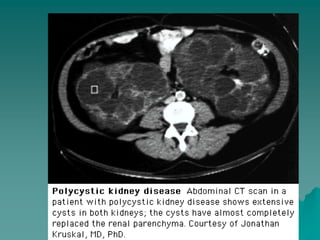

PRINCIPAIS CAUSAS DEIRC  DOENÇAS SISTÊMICAS:  Diabetes mellitus.  H. arterial .  Doenças auto- imunes ( LES, Vasculites).  Amiloidose.  Mieloma múltiplo.  DOENÇAS HEREDITÁRIAS:  Rins policísticos.  Síndrome de Alport.  Cistinose.